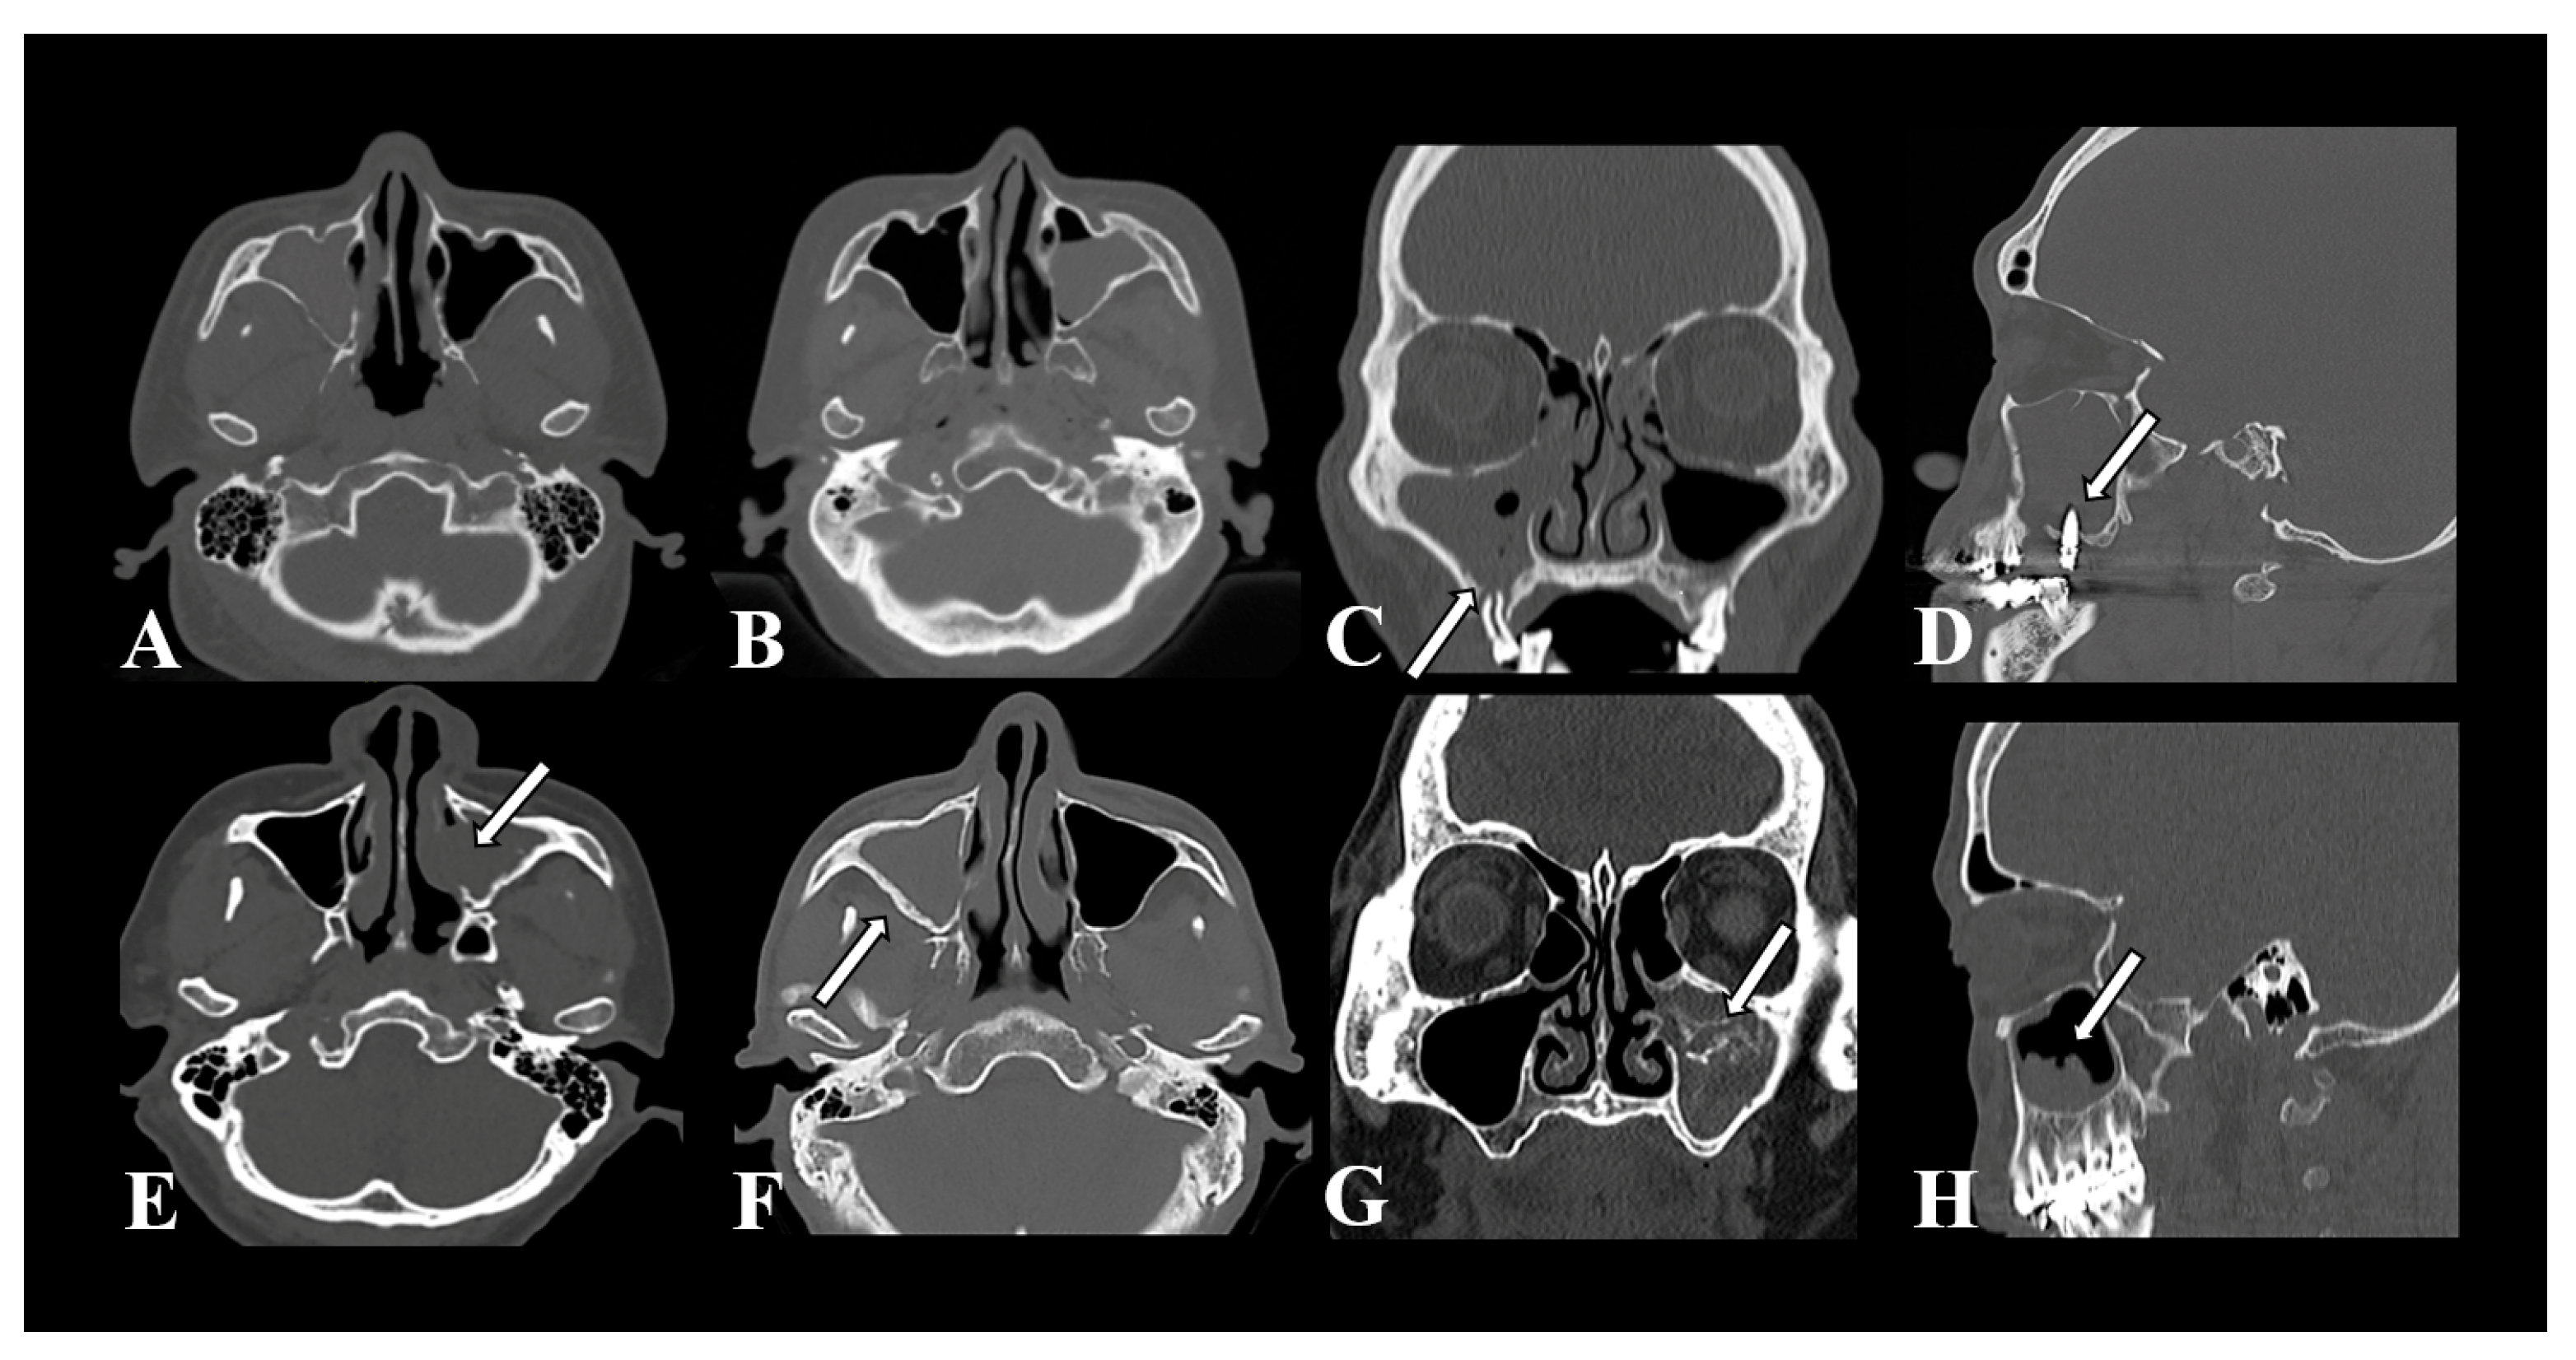

3.2. Features of CT Imaging

| Irregular surface, n (%) | 41 (42.3) | 14 (8.9) | <0.001 *** |

| Erosion of medial sinus wall, n (%) | 53 (54.6) | 12 (7.6) | <0.001 *** |

| Sclerosis of lateral sinus wall, n (%) | 88 (90.7) | 109 (69.0) | <0.001 *** |

| Intralesional hyperdensity, n (%) | 79 (81.4) | 9 (5.7) | <0.001 *** |